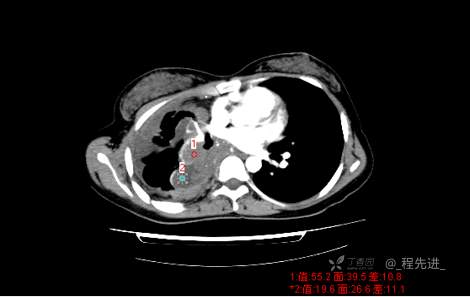

患者性别:女

患者年龄:26岁

简要病史:反复胸闷、气喘、咳嗽半年